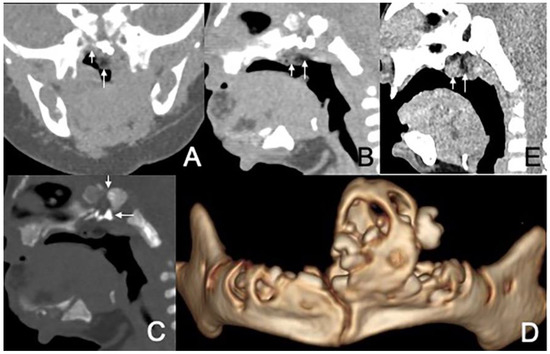

Figure 2. CT of a 1-month and 16-day girl presenting with throat congestion 29 days after birth. (A,B) Sagittal and axial CT, displayed in the soft-tissue window, shows a sausage-like fat density mass (short arrow) with a soft tissue density core (long arrow) originating from the left lateral pharyngeal wall. (C) Axial, postcontrast CT, displayed in the soft-tissue window, shows that the lesion’s stalk is slightly enhanced (arrow), but the rest of the lesion is not enhanced.

The size of masses varied from 0.6 to 4.3 cm. There were 11 (78.6%) cases with the largest diameter of the mass greater than 2 cm. The shapes of the masses were varied. Eleven (78.6%) cases presented with typical pedicled masses containing fat and a central core of soft tissue, including sausage-like masses in five (35.7%) cases, tongue-like masses in four (28.6%) cases, and pear-like masses in two (14.3%) cases. Of the eight patients who underwent MRI scans, there were five (62.5%) patients whose masses had high signal intensity on T1-weighted and T2-weighted sequences with a low-signal central core whose signal intensities were similar to those of muscles. The high signal intensities on all sequences were similar to the fat signals and attenuated by fat suppression. The central core demonstrated mild enhancement following intravenous gadolinium administration, while the surrounding components of the fat signals demonstrated no enhancement in one case (Figure 1). There was no reduced diffusion of the five patients who underwent DWI. Via CT, there were 10 (83.3%) cases whose masses appeared as well-circumscribed fat attenuation masses surrounding a central core of soft tissue. The central core was mildly enhanced following intravenous iodixanol administration, but the fat components were not enhanced in one case (Figure 2). There were five patients who received both MRI and CT.

In addition, three (21.4%) cases presented with irregular shapes the MRI or CT findings that were atypical. One case presented with a sausage-like mass in the right nasal vestibule and nasal limen that was mainly high-signal with multiple filament-like low signals inside on T1-weighted and T2-weighted MRI (Figure 3). One case presented with a multilayered circumferential mass in the left parapharyngeal space that was soft tissue, lipid, fibrous capsule, and soft tissue intense from inside to outside, and the mass extended to the left external auditory canal and middle ear (Figure 4). One case presented with irregular fat and soft tissue density mass originating from the back side of the left soft palate (Figure 5).

Upon MRI, most of the masses were found to have heterogeneous high signal intensity on T1-weighted and T2-weighted sequences with a low-signal central core whose signal intensities were similar to those of muscles. The high signal intensities on all sequences were similar to the fat signals and attenuated by fat suppression. The central core demonstrated mild enhancement following intravenous gadolinium administration, while the surrounding components of the fat signals demonstrated no enhancement. The central core helps us trace the origin of the mass, which is important for the choice of surgical method. Characteristic imaging features on CT include well-circumscribed masses containing fat and linear soft tissue–density components centrally that correspond to the fibrovascular stalk [2]. The central core was mildly enhanced, as expected for fibrous tissue, but the fat components were not [23]. These findings corresponded well with the MRI and CT features previously described [24,25]. Intracranial or intraspinal extension was not found in any of the lesions in the present study, which was consistent with existing reports.